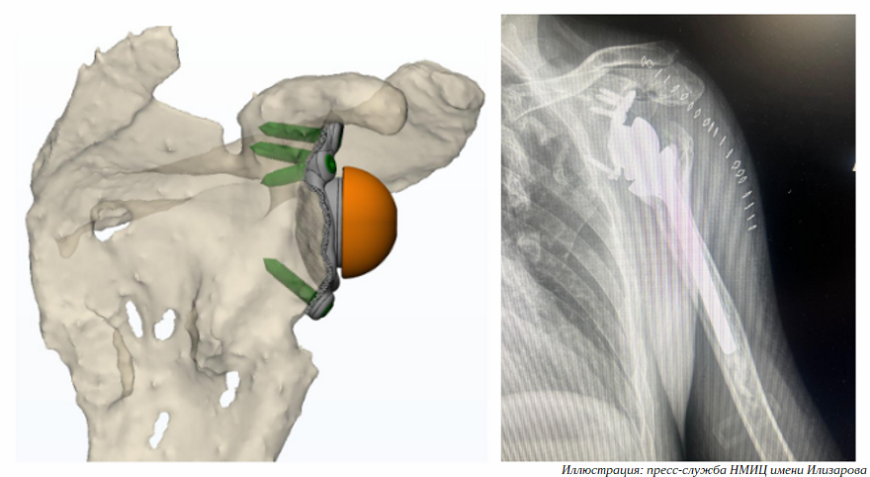

Врачи Центра Илизарова вернули пациенту подвижность руки с помощью 3D-печатного эндопротеза

Титановый имплантат изготовлен по антропометрическим данным пациента. Как только индивидуальный протез суставного отростка лопатки был доставлен в Курган, хирурги отделения №8 Национального медицинского исследовательского центра травматологии и ортопедии имени академика Г. А. Илизарова провели сложную операцию по установке персонифицированной конструкции.

Пациент обратился в центр с жалобами на боли в плечевом суставе и ограничение движений, сообщает пресс-служба НМИЦ имени Илизарова. Мужчина не мог пользоваться рукой в быту и профессиональной деятельности из-за ранее полученной боевой травмы. Обследование показало, что в результате травмы возникла не только деформация проксимального отдела плеча, но и сформировался тотальный дефект суставного отростка лопаточной кости. Этот отросток попросту отсутствовал.

«В такой ситуации невозможно надежно фиксировать лопаточный компонент. Даже если бы это получилось, биомеханика эндопротеза плечевого сустава была бы крайне нарушена. Поэтому совместно с московскими инженерами нами был разработан индивидуальный лопаточный компонент реверсивного эндопротеза с помощью аддитивных технологий», — рассказал руководитель Клиники реконструктивно-восстановительной хирургии крупных суставов НМИЦ имени Илизарова Николай Чирков.

В ходе операции врачи столкнулись с рядом серьезных трудностей: вся полость плечевого сустава и окружающие участки были заполнены плотной рубцовой тканью, поэтому перед установкой протеза хирургам предстояло ликвидировать фиброзно-спаечный процесс, что и было успешно выполнено. Хирурги зафиксировали лопаточный компонент, компенсировали все костные дефекты и установили реверсивный протез плечевого сустава. Мышцы пациента приведены в тонус, плечевой сустав стал мобильным, мужчина вновь может полноценно пользоваться рукой.